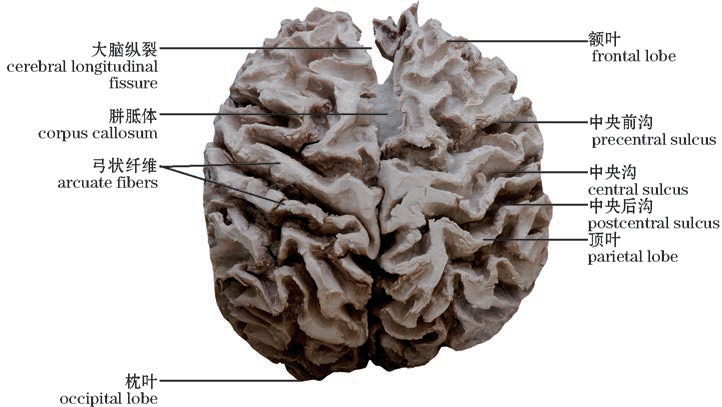

图10-42 大脑髓质(上面观)

The cerebral medulla(Superior view)